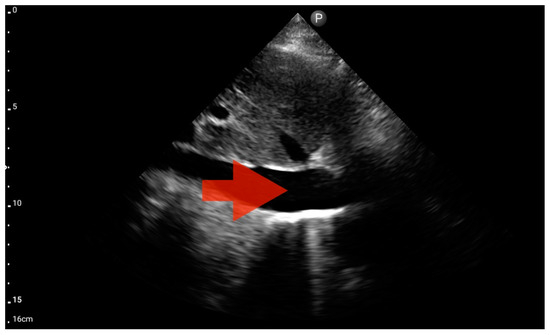

Figure 12.

Left ventricle hypokinesis; position: apical four-chamber (FATE protocol). Sector probe; the red arrow marks the left ventricle, which, during the examination, showed signs of reduced ejection fraction and hypokinesis (source: author’s material—DK).